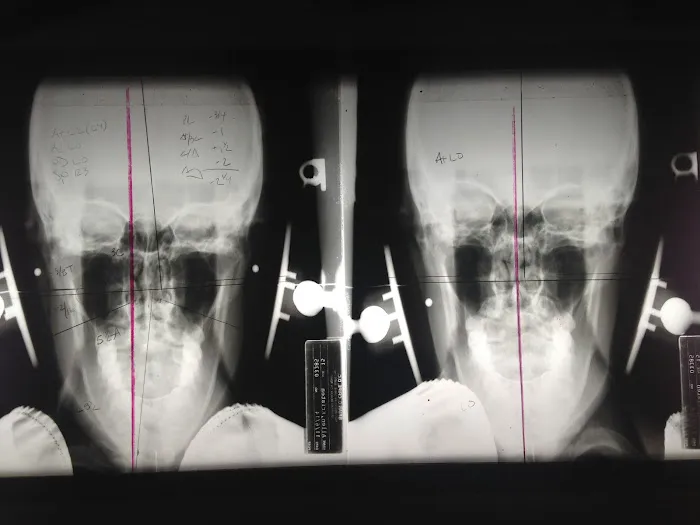

On-Site Digital X-rays: To ensure the utmost precision, the clinic offers in-house digital X-ray imaging. This allows for an accurate diagnosis and a customized treatment plan tailored to each patient's unique misalignment.